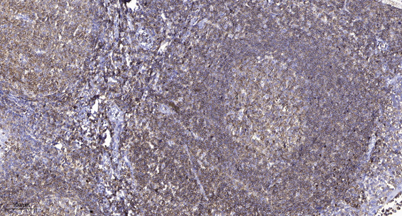

IHC

Recomended Dilution IHC-p 1:50-200, WB 1:500-2000